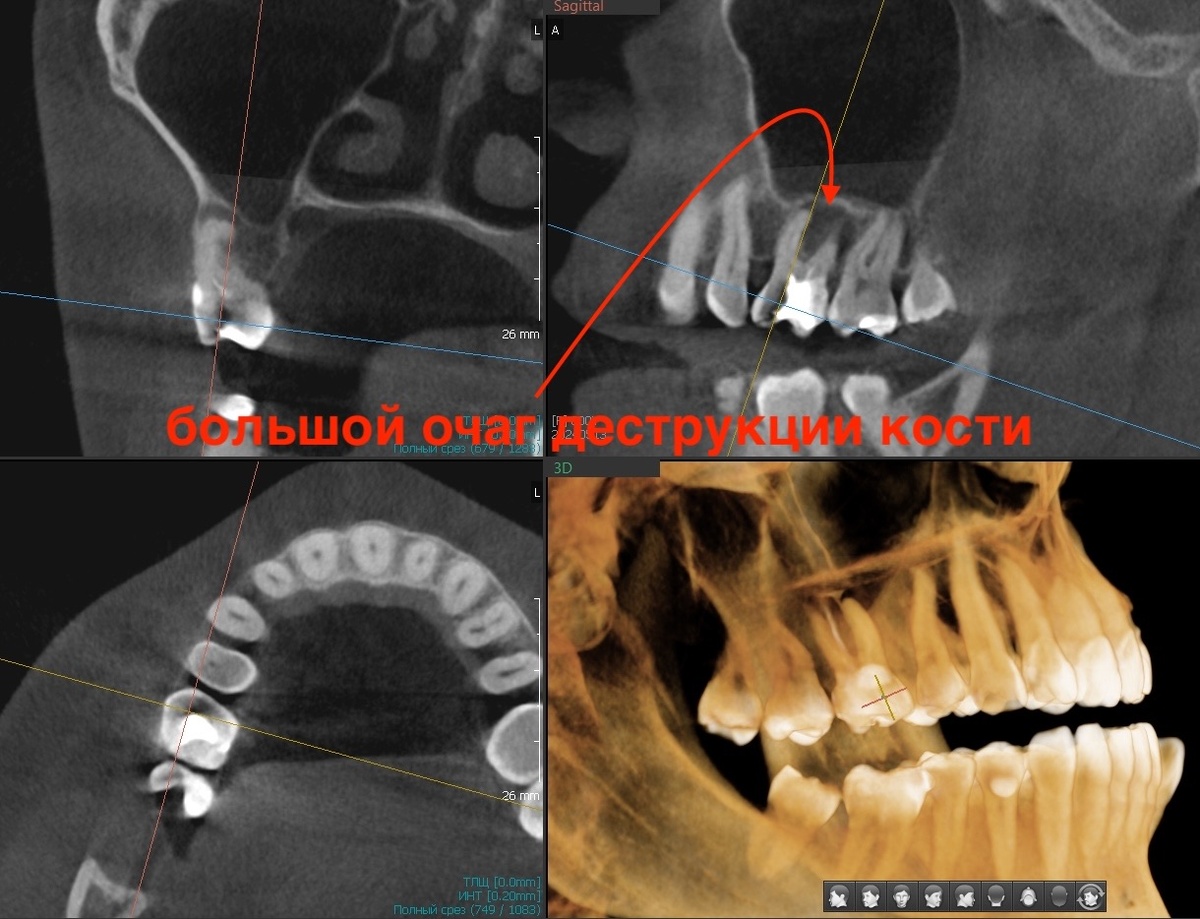

Периодонтит 1.6 зуба, 2024 год

Март 2025 - через 9 месяцев. Делаем КТ и видим положительную динамику:

КТ через 9 месяцев после лечения

Очаг деструкции уменьшился, кость восстанавливается. Но кость зажила ещё не полностью.